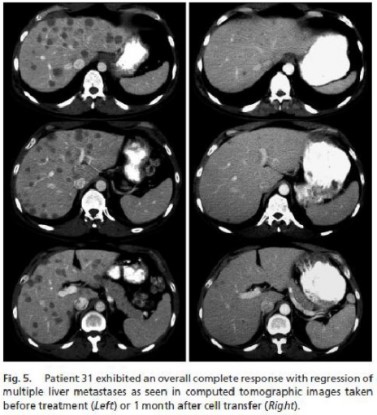

1例多发肝癌转移的病例,回输DC-CIK细胞后得到了很大的缓解,机体各方面症状减轻,生活质量有了很大的提高。